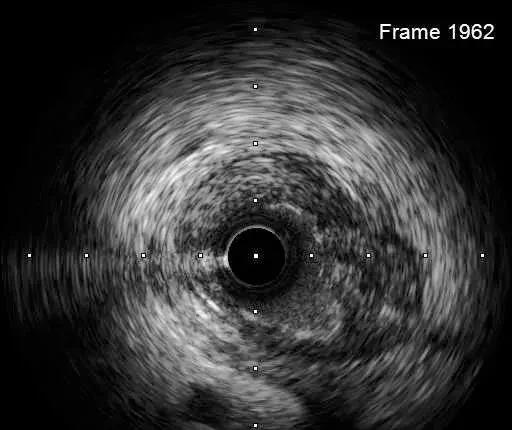

IVUS-2 预扩张后小夹层和血肿

Dia开口

Dia近段

LAD闭塞段

LAD近段

LAD开口